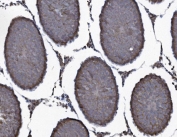

IHC staining of FFPE rat testis tissue with SEC14L3 antibody. HIER: boil tissue sections in pH8 EDTA for 20 min and allow to cool before testing.